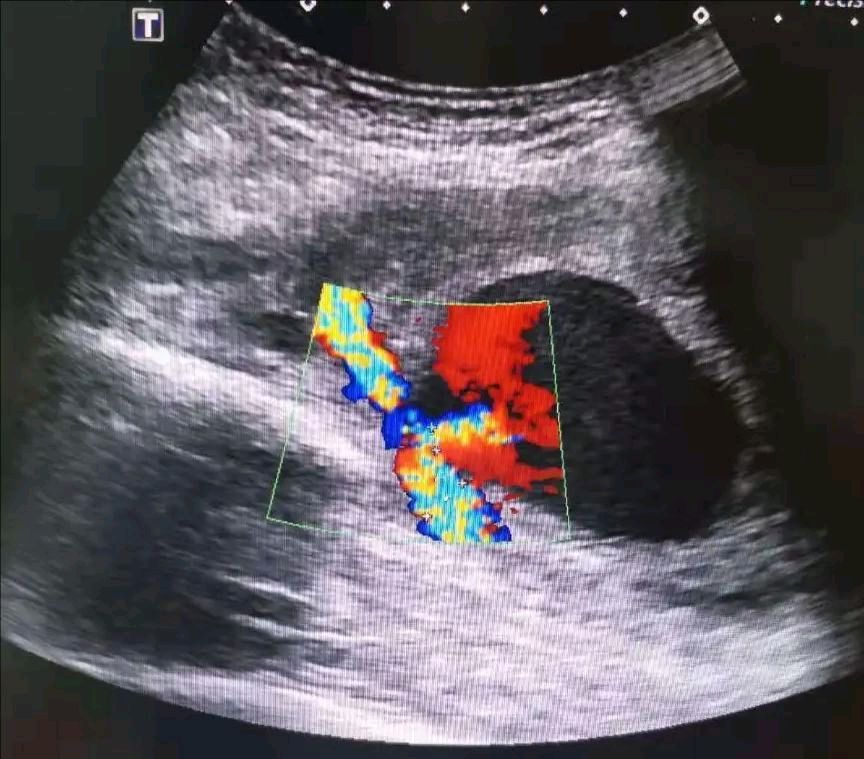

超声检查